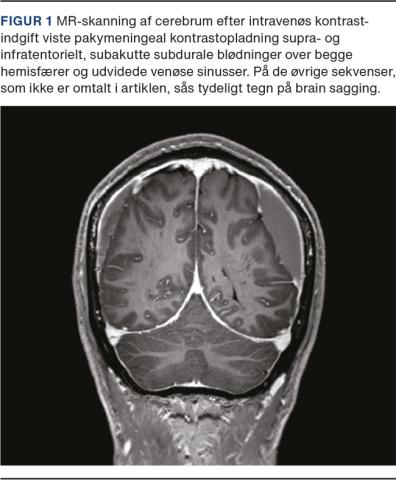

En 52-årig tidligere rask mand debuterede med pludselig indsættende svimmelhed, høretab, tinnitus og trykkende hovedpine på en flyvetur i maj 2019. Da der var mistanke om barotraume søgte patienten otolog, men undersøgelse og rutine-CT af cerebrum og MR-skanning af cerebrum (MR-C) blev beskrevet som normale. På grund af vedvarende symptomer blev der foretaget en ny MR-C, nu med gadolinium i juni 2019, og her påvistes pakymeningeal opladning, men af uvisse grunde blev der ikke foretaget yderligere udredning. Patienten blev senere henvist til neurolog, da generne fortsatte, og en ny MR-C den 2. januar 2020 viste bilaterale subdurale hæmatomer og pakymeningeal opladning (Figur 1). Da der ikke var masseeffekt, afstod man fra neurokirurgisk evakuering af hæmatomerne. Der var ingen andre traumer eller risikofaktorer, og da generne var klart ortostatiske, dvs. intense efter 5-10 min i oprejst stilling og minimale i liggende stilling, fik man nu mistanke om SIH. Lumbal blood patch (BP) den 6. januar 2020 havde god effekt, men der kom gradvist recidiv af hovedpinen og svimmelheden efter få uger. Ny BP den 6. februar 2020 gav hurtig symptomfrihed fraset let tinnitus. MR-C den 19. maj 2020 og den 22. august 2020 viste delvis regression af forandringerne. Ved sidste opfølgning i juli 2021 var generne helt remitteret, og patienten var velbefindende.

SIH bør overvejes hos yngre personer, der debuterer med ny, akut og ortostatisk hovedpine, tinnitus, hørenedsættelse og/eller svimmelhed [2]. Tilstanden beskrives som spontan, men der kan være et mindre barotraume som i aktuelle sygehistorie eller et mindre vrid- eller forløftningstraume i anamnesen [2]. Radiologisk ses oftest pakymeningeal opladning, bilaterale subdurale hygromer, og/eller brain sagging med smalle præpontine cisterner, komprimeret tredje ventrikel og cerebellare tonsiller samt formindsket pontomesencefal vinkel [4].